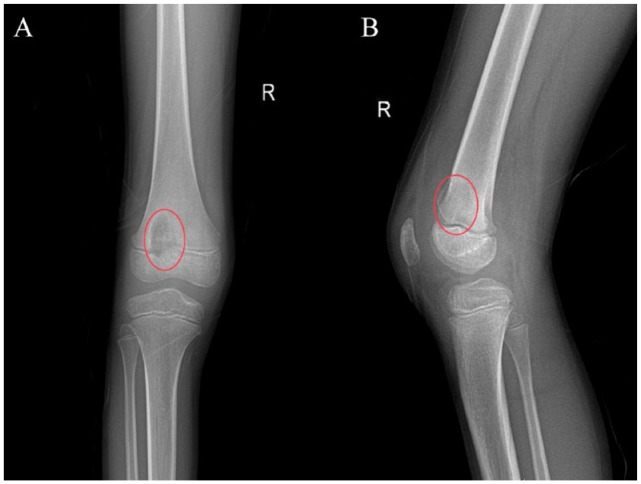

Case presentation: We report a rare case of a 9-year-old male diagnosed with right knee tuberculosis after enduring severe symptoms for several months. Despite multiple negative biopsies and aspirates during initial debridement surgeries, a biopsy taken 6 months later confirmed the presence of Mycobacterium tuberculosis (MTB). The patient was subsequently treated with debridement and anti-tubercular therapy.

Conclusion: This case underscores the critical need to consider tuberculosis in patients presenting with chronic bone pain to avoid misdiagnosis, particularly in the developing world. The atypical presentation of osteoarticular tuberculosis in this young patient emphasizes the need for healthcare professionals to recognize subtle symptoms. Advanced imaging studies like MRI and microbiological evaluations, including site biopsies, are essential for accurate diagnosis. Increased awareness and collaborative research are crucial to improving the understanding and management of pediatric osteoarticular tuberculosis and extrapulmonary tuberculosis.